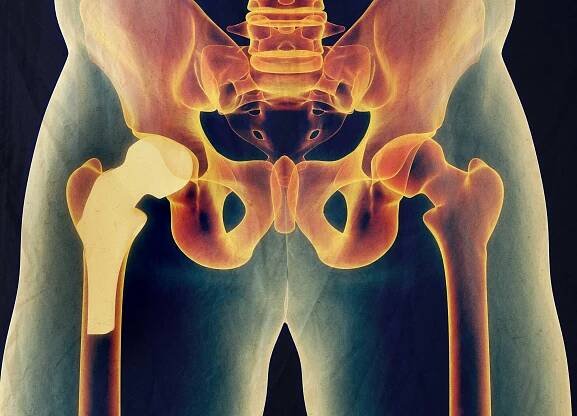

Operace kyčle se provádí za účelem náhrady poškozeného nebo opotřebovaného kyčelního kloubu umělou náhradou. Během zákroku se odstraní poškozené části kloubu a nahradí se komponenty z kovu, keramiky nebo plastu. Tento proces pomáhá obnovit funkci kloubu a zmírnit bolest. Operace se provádí pod celkovou nebo…

Totální endoprotéza kyčle (TEP) je chirurgický zákrok, při kterém je nahrazena poškozená kyčelní kloubní část umělou náhradou, tzv. endoprotézou...

Totální endoprotéza kyčle – moderní operace pro návrat k pohybu…